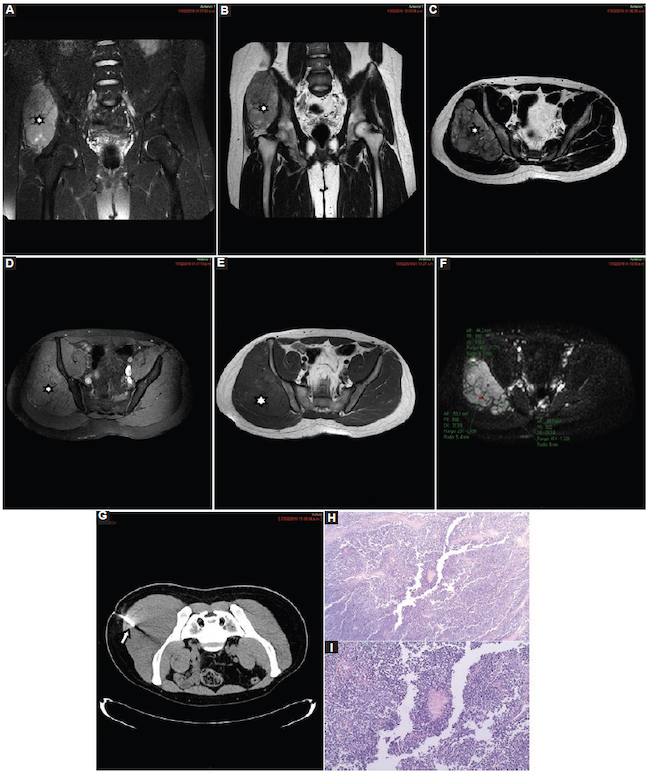

Sarcoma de Ewing: fueron cuatro casos, con un valor medio de CDA de 0,75 ± 0,19 × 10−3 mm2/s (0,500,90) (Fig. 17), de los cuales fueron dos en el fémur, uno en la pelvis y uno en la pierna (extraóseo).

El sarcoma de Ewing fue el tumor que mostró el CDA más bajo. Es un miembro de la familia de los tumores de células pequeñas, redondas y azules, caracterizada por ser un grupo de neoplasias de apariencia primitiva o embrionaria, por lo que estimamos que ante eventuales mediciones de un CDA de tan bajo valor estas neoplasias deberían ser consideradas en el diagnóstico diferencial.